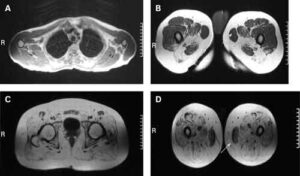

Uno studio finanziato da Telethon rimette in discussione le basi genetiche della distrofia facio-scapolo-omerale, malattia caratterizzata da debolezza muscolare progressiva...